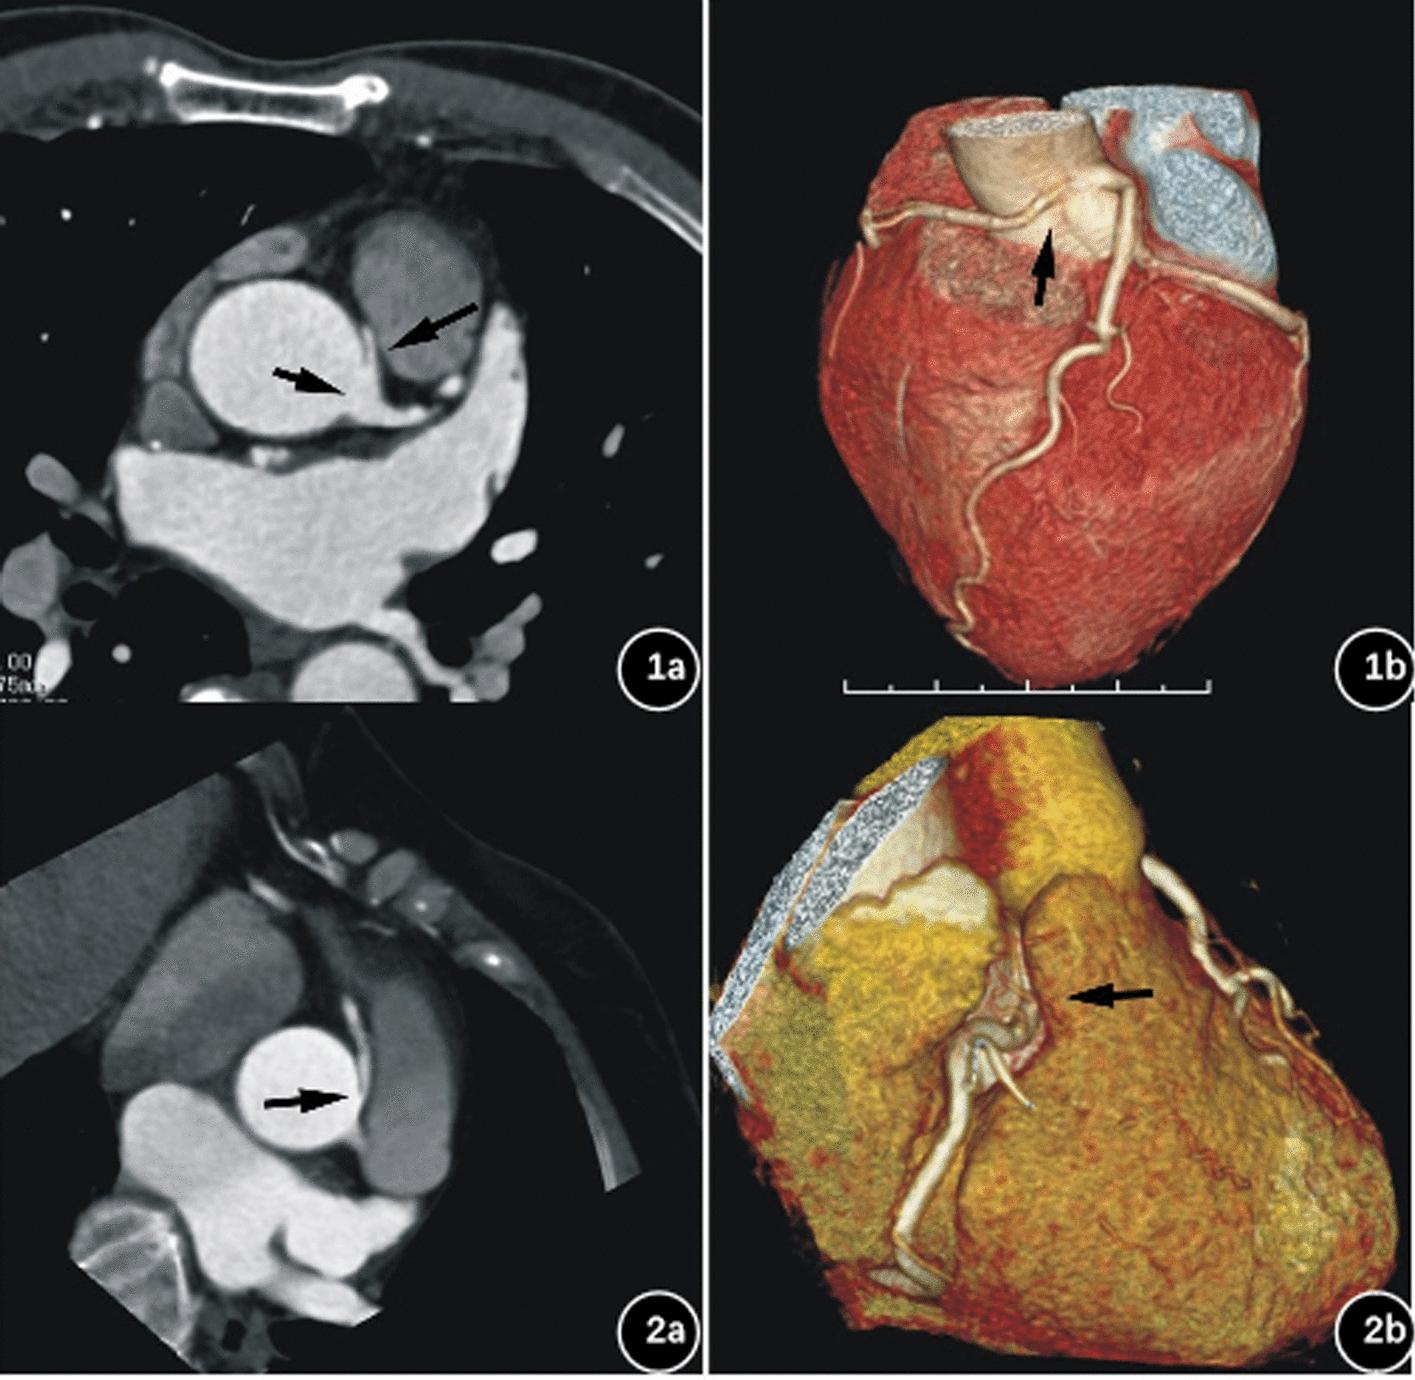

Anomalous origin of coronary artery is a common coronary artery anatomy anomaly. The anomalous origin of the coronary artery may lead to problems such as narrowing of the coronary arteries at the beginning of the coronary arteries and abnormal alignment, which may lead to myocardial ischemia due to the compression of the coronary arteries. Clinical symptoms include chest tightness and dyspnea, with angina pectoris as a common symptom that can be life-threatening. Timely and accurate diagnosis of anomalous coronary artery origin is of great importance. Coronary computed tomography angiography (CCTA) can provide detailed information on the characteristics of coronary arteries. Therefore, we combined CCTA and artificial intelligence (AI) technology to analyze the CCTA image features and clinical features of patients with anomalous origin of the right coronary artery to predict angina pectoris and the relevance of different features to angina pectoris.

冠状动脉异常起源是一种常见的冠状动脉解剖异常。冠状动脉的异常起源可能导致冠状动脉起始处狭窄和异常排列等问题,这可能导致冠状动脉受压引起心肌缺血。临床症状包括胸闷和呼吸困难,以心绞痛为常见症状,可能危及生命。及时准确地诊断冠状动脉异常起源非常重要。冠状动脉计算机断层血管造影(CCTA)可以提供冠状动脉特征的详细信息。因此,我们结合 CCTA 和人工智能(AI)技术来分析右冠状动脉异常起源患者的 CCTA 图像特征和临床特征,以预测心绞痛和不同特征与心绞痛的相关性。